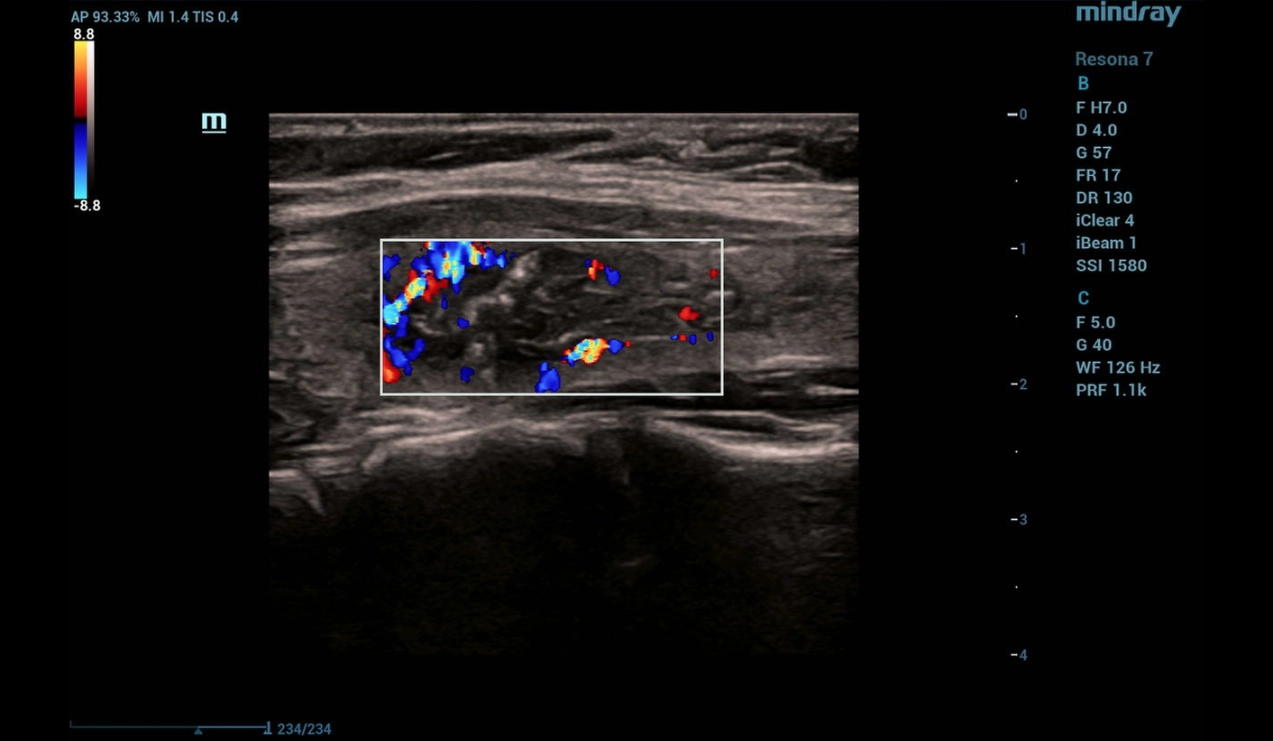

In Color Flow Doppler (CFD) there is no blood flow in the focal mass with the presence of single perinodular vessels (Fig.2)

throid-sclerotherapy-fig2-pc

Figure 2. CFD image of thyroid

As the necessary exposure was completed, the sclerosant was evacuated followed by completion of the manipulation and control ultrasound. In - mode a heterogeneous focal formation of the thyroid gland with absence of cystic component was detected (Fig. 8). CFD mode determines absence of blood flow in the focal mass with preserved perinodular vessels (Fig. 9). Strain elastography reveals elastographic heterogeneity of the focal mass with predominance of a soft tissue component (Fig. 10).

Figure 9. CFD of a focal thyroid lesion after sclerotherapy